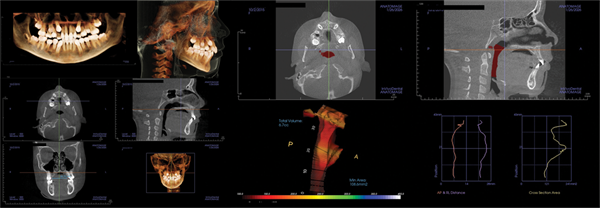

Patient two: Palatal expansion and Phase I (Figs. 4–7)

The second patient was a 7½-year-old boy referred for crowding. During the examination, it was noted that he snored, was a mouth breather, and had nocturia.

The facial examination showed well-balanced jaw relationships and narrow smile bones, resulting in a lack of a full smile. The panoramic X-ray showed anterior crowding, adequate room for the second molars, and a Class II tendency. The lateral X-ray confirmed the Class II tendency.

The airway view on CBCT demonstrated an MCA of 60 and enlarged adenoids. The palatal width was 28 mm. The parents were advised to consult an ENT surgeon, and Phase I treatment was initiated to include palatal expansion.

Following expansion, and before completing Phase I treatment with aligners, the MCA increased to more than 200 mm. The palatal width increased to 34 mm. The ENT surgeon did not recommend surgical intervention at that time. The parents reported improved sleep and resolution of enuresis.